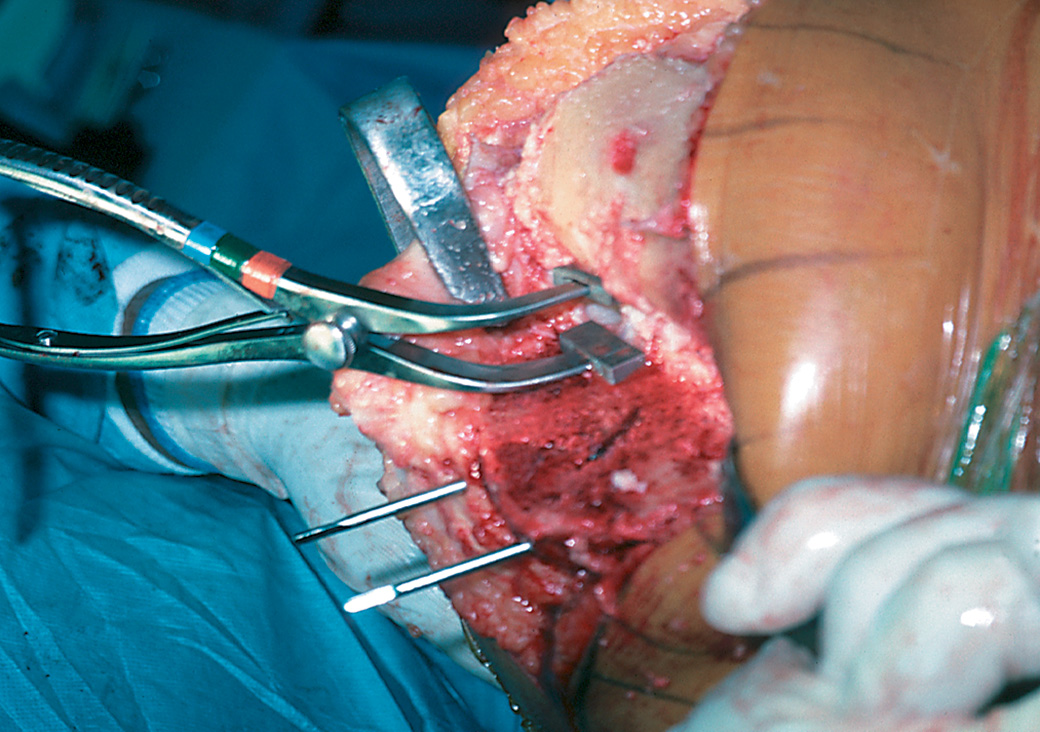

Femoral Tibial Spreader – Medium with Speed Lock and Grooved Pads

Speed lock modification designed by Nasim A. Rana, MD

Helps separate the femur and tibia during total knee replacement surgery

Speed lock helps allow precise control and prevent unintended release.

Designed to remain in position, with the femur and tibia separated, without the need of an assistant, and to minimize crushing the bone, even if osteoporotic. A wide unobstructed view of the posterior compartment is possible. Osteophytes on the posterior condyles of the femur and tibia can be seen and removed.